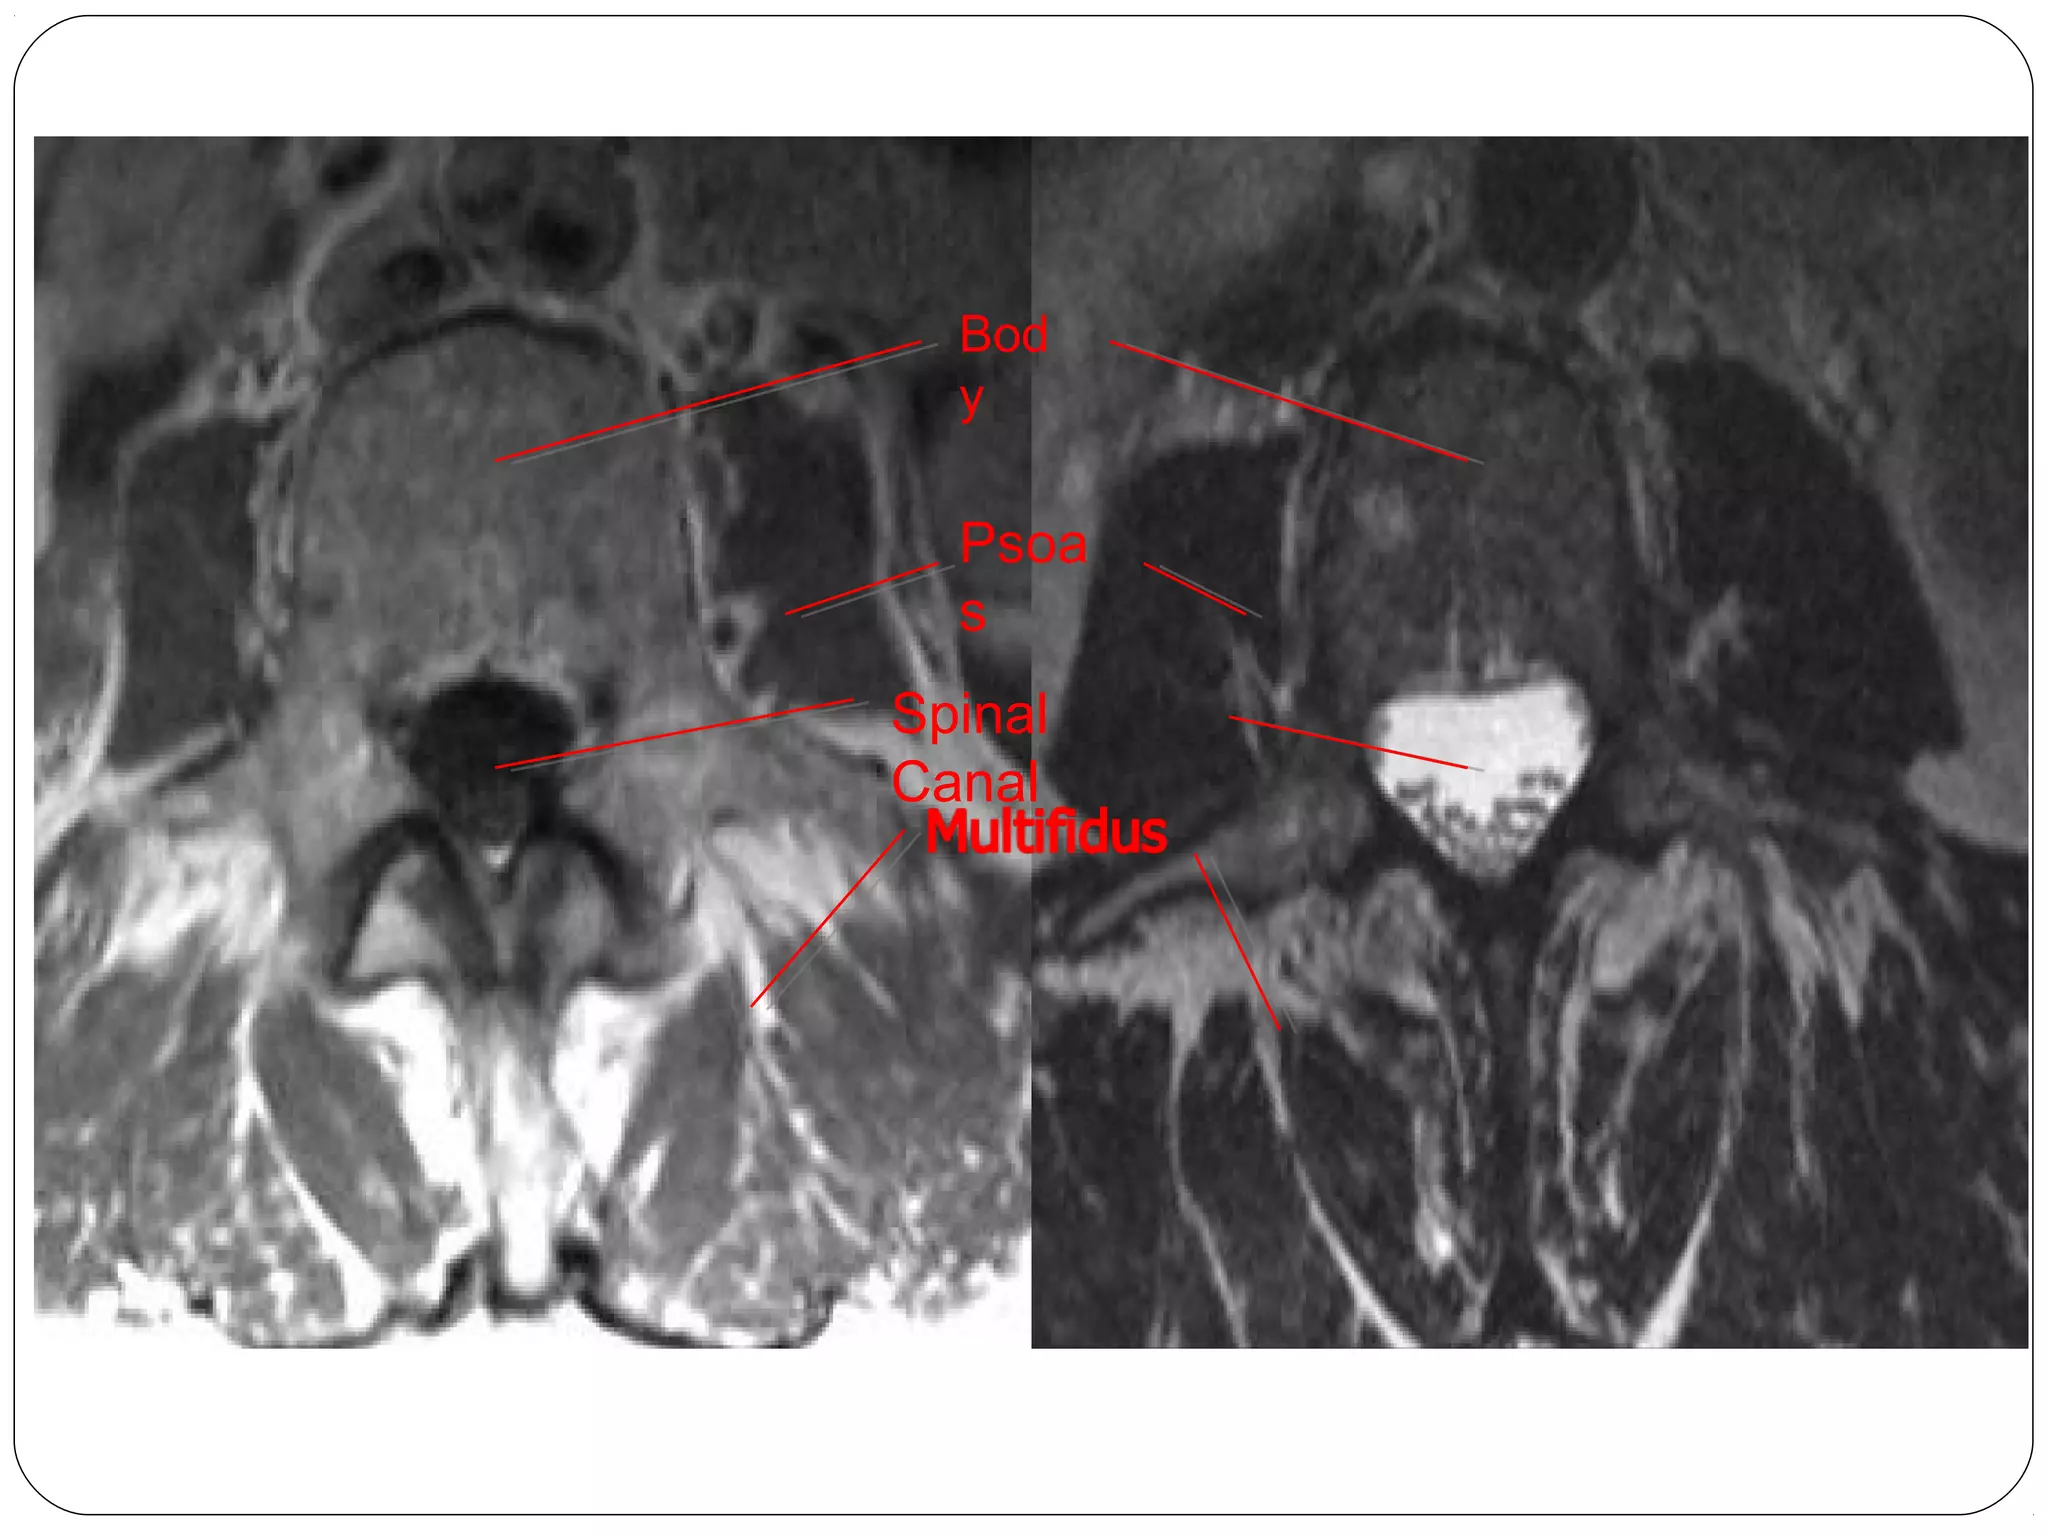

Lumbar Spine – MRI Axial

Bod

y

Psoa

s

Spinal

Canal

Herniated

disc

• 73.

Axial T1 body Axial T1 disc AxialT2 body Axial T2 disc Lumbar Spine – MRI Axial